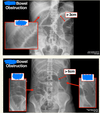

162

what are these lines in these bowl obstructions. where are each of the obstructions?

what is the red arrow pointing to? what is the likely cause?

free air under the diaphram. perforation

what is a normal diameter ofL small intestine, large intestine, caecum